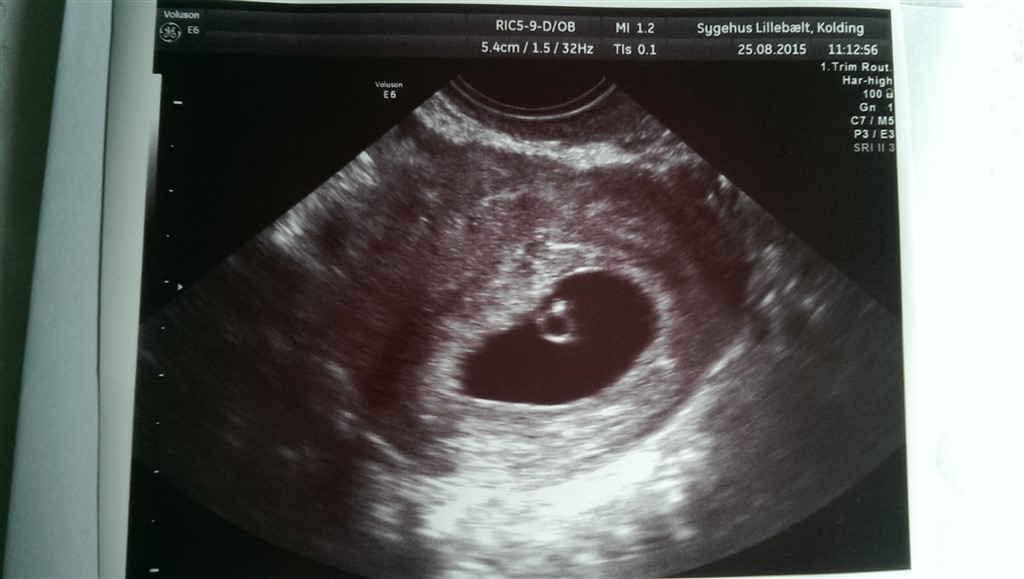

Min graviditet udvikler sig som dent skal, og på scanningen kunne vi se en fin blommesæk og et lille embryo, som målte lige knap 2 mm

Lægen vurderede jeg må være omkring 5+